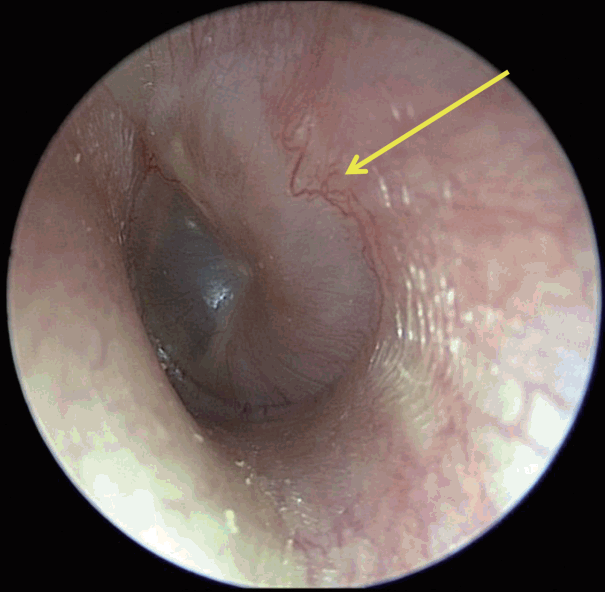

문진상 좌측 청력저하를 호소하였고 그 외 이루, 이통 및 현훈 등의 증상은 호소하지 않았다. 신체 검진상 안면 비대칭은 없었고, 고막 내시경 검사상 양측 고막에서 천공은 보이지 않았고, 좌측 고막에 중이강 내 저류액 소견 및 고막 상방의 팽윤 소견이 관찰되었다(Fig. 1). 순음청력검사에서 우측 기도청력 20 dB HL, 골도청력 20 dB HL, 좌측 기도청력 30 dB HL, 골도청력 25 dB HL으로 확인되었다(이상 6분법) (Fig. 2). 조영증강 측두골 전산화단층촬영 영상에서 좌측 중이강 내 연조직 강도의 음영이 관찰되었으며 하고실을 채우고 있는 음영의 경우 조영증강이 동반되는 반면에, 상고실에서 관찰된 음영의 경우 조영증강이 되지 않았다. 이관 및 이관 입구부위는 폐쇄된 소견은 관찰되지 않았고 비인두강 내 특이소견도 관찰되지 않았다(Fig. 3). 위 소견들을 바탕으로 좌측 진주종 및 삼출성 중이염 의심하에 좌측 내시경 및 현미경을 이용한 시험적 개방술을 통한 진주종 제거를 계획하였고 필요시 공동폐쇄 유양동 절제술 및 고실 성형술을 고려하여 수술을 준비하였다.